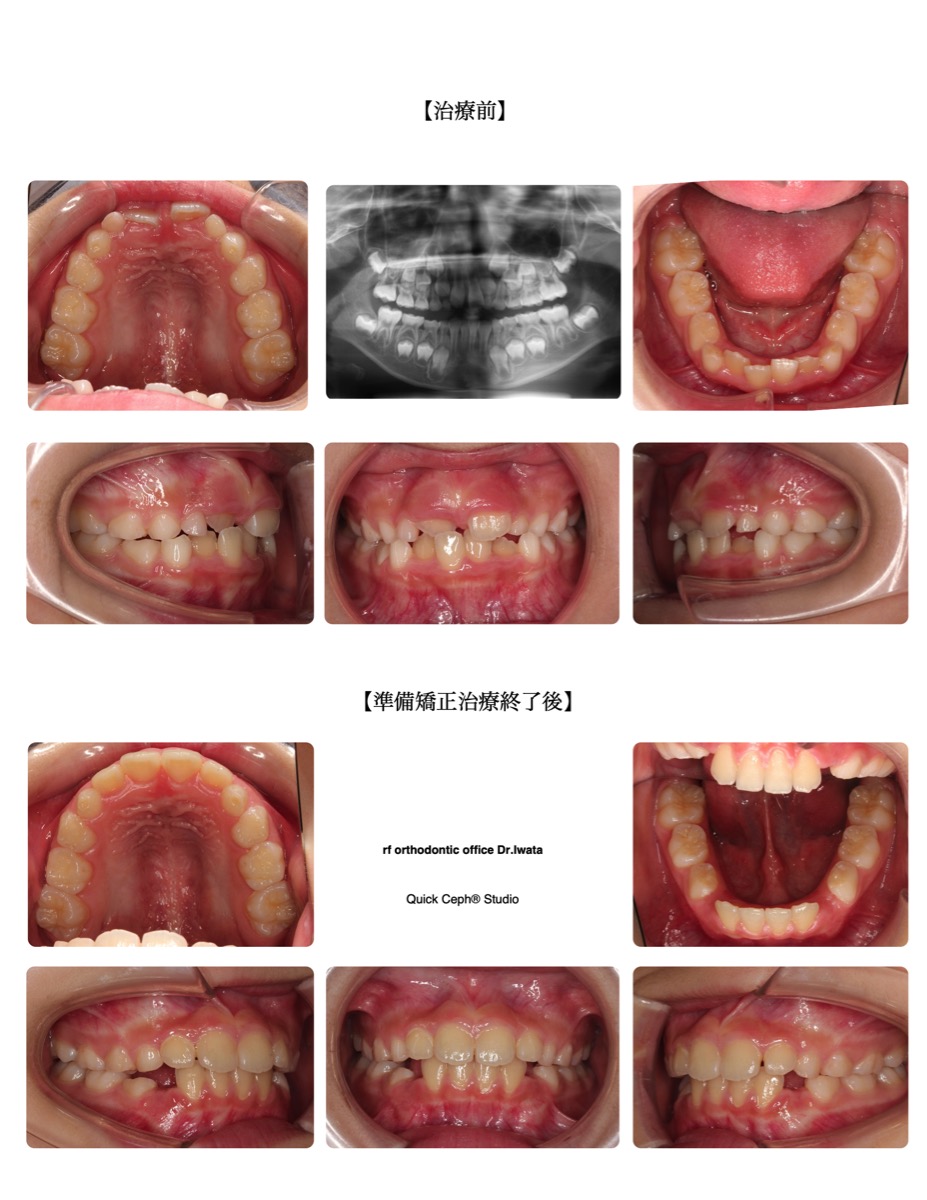

【主訴】上の歯が1本内側から出てきた。下の前歯がでこぼこになっている。

【主な症状】反対咬合 叢生

| 治療期間・回数 | 15ヶ月・13回 |

| 年齢 | 7歳 |